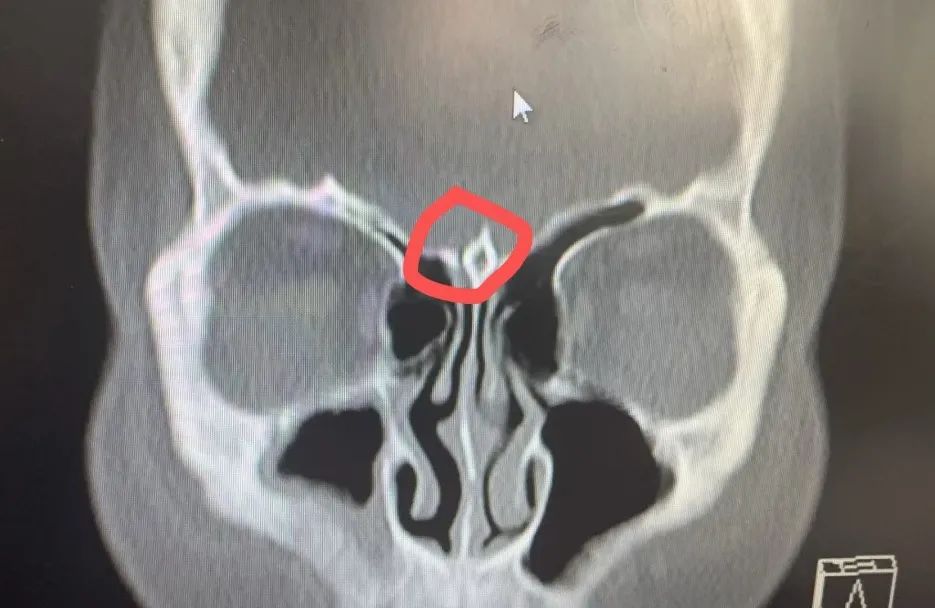

經(jīng)過充分的術(shù)前準(zhǔn)備,耳鼻咽喉頭頸外科陸訓(xùn)彪主任帶領(lǐng)團(tuán)隊(duì)為患者實(shí)施了經(jīng)鼻內(nèi)鏡腦脊液鼻漏修補(bǔ)術(shù),術(shù)中發(fā)現(xiàn)嗅裂頂部存在約2mm大小的白色略透明的膜狀膨出物,考慮腦膜腦膨出。術(shù)中用中鼻甲粘膜移植覆蓋瘺口,并特別注意保護(hù)周圍神經(jīng)和血管,精心處理好瘺口周圍組織,力求最大程度減少復(fù)發(fā)風(fēng)險(xiǎn)。經(jīng)過團(tuán)隊(duì)的共同努力,手術(shù)圓滿成功,術(shù)中僅出血約20ml。